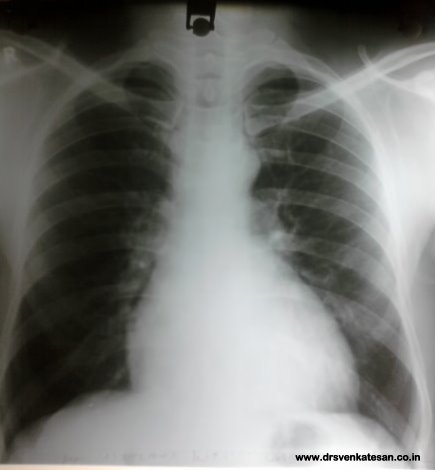

By statistics cardiomegaly   often implies  ventricular enlargement (especially left ventricular) .Right ventricle generally do not enlarge the  CT ratio until late stages .

More important  is the impact of right atrial enlargement on the CT ratio. Here was a  patient referred to echo lab for evaluation of cardiomegaly

The x-ray chest  was suggesting a definite LV enlargement.  To my surprise  the LV was perfectly  measuring a normal dimension .

The right atrium was huge and measuring  more than 5 cms . This increased the CTR.

Cardimegaly in  X- ray chest do not  necessarily  mean ventricular enlargement.

Pure atrio-megaly  especially right atrial enlargement can dramatically increase the CT ratio.

This is not a big  discovery , still fellows need   to reinforce  this fact  , as  mistakes are most often committed in well  known things !